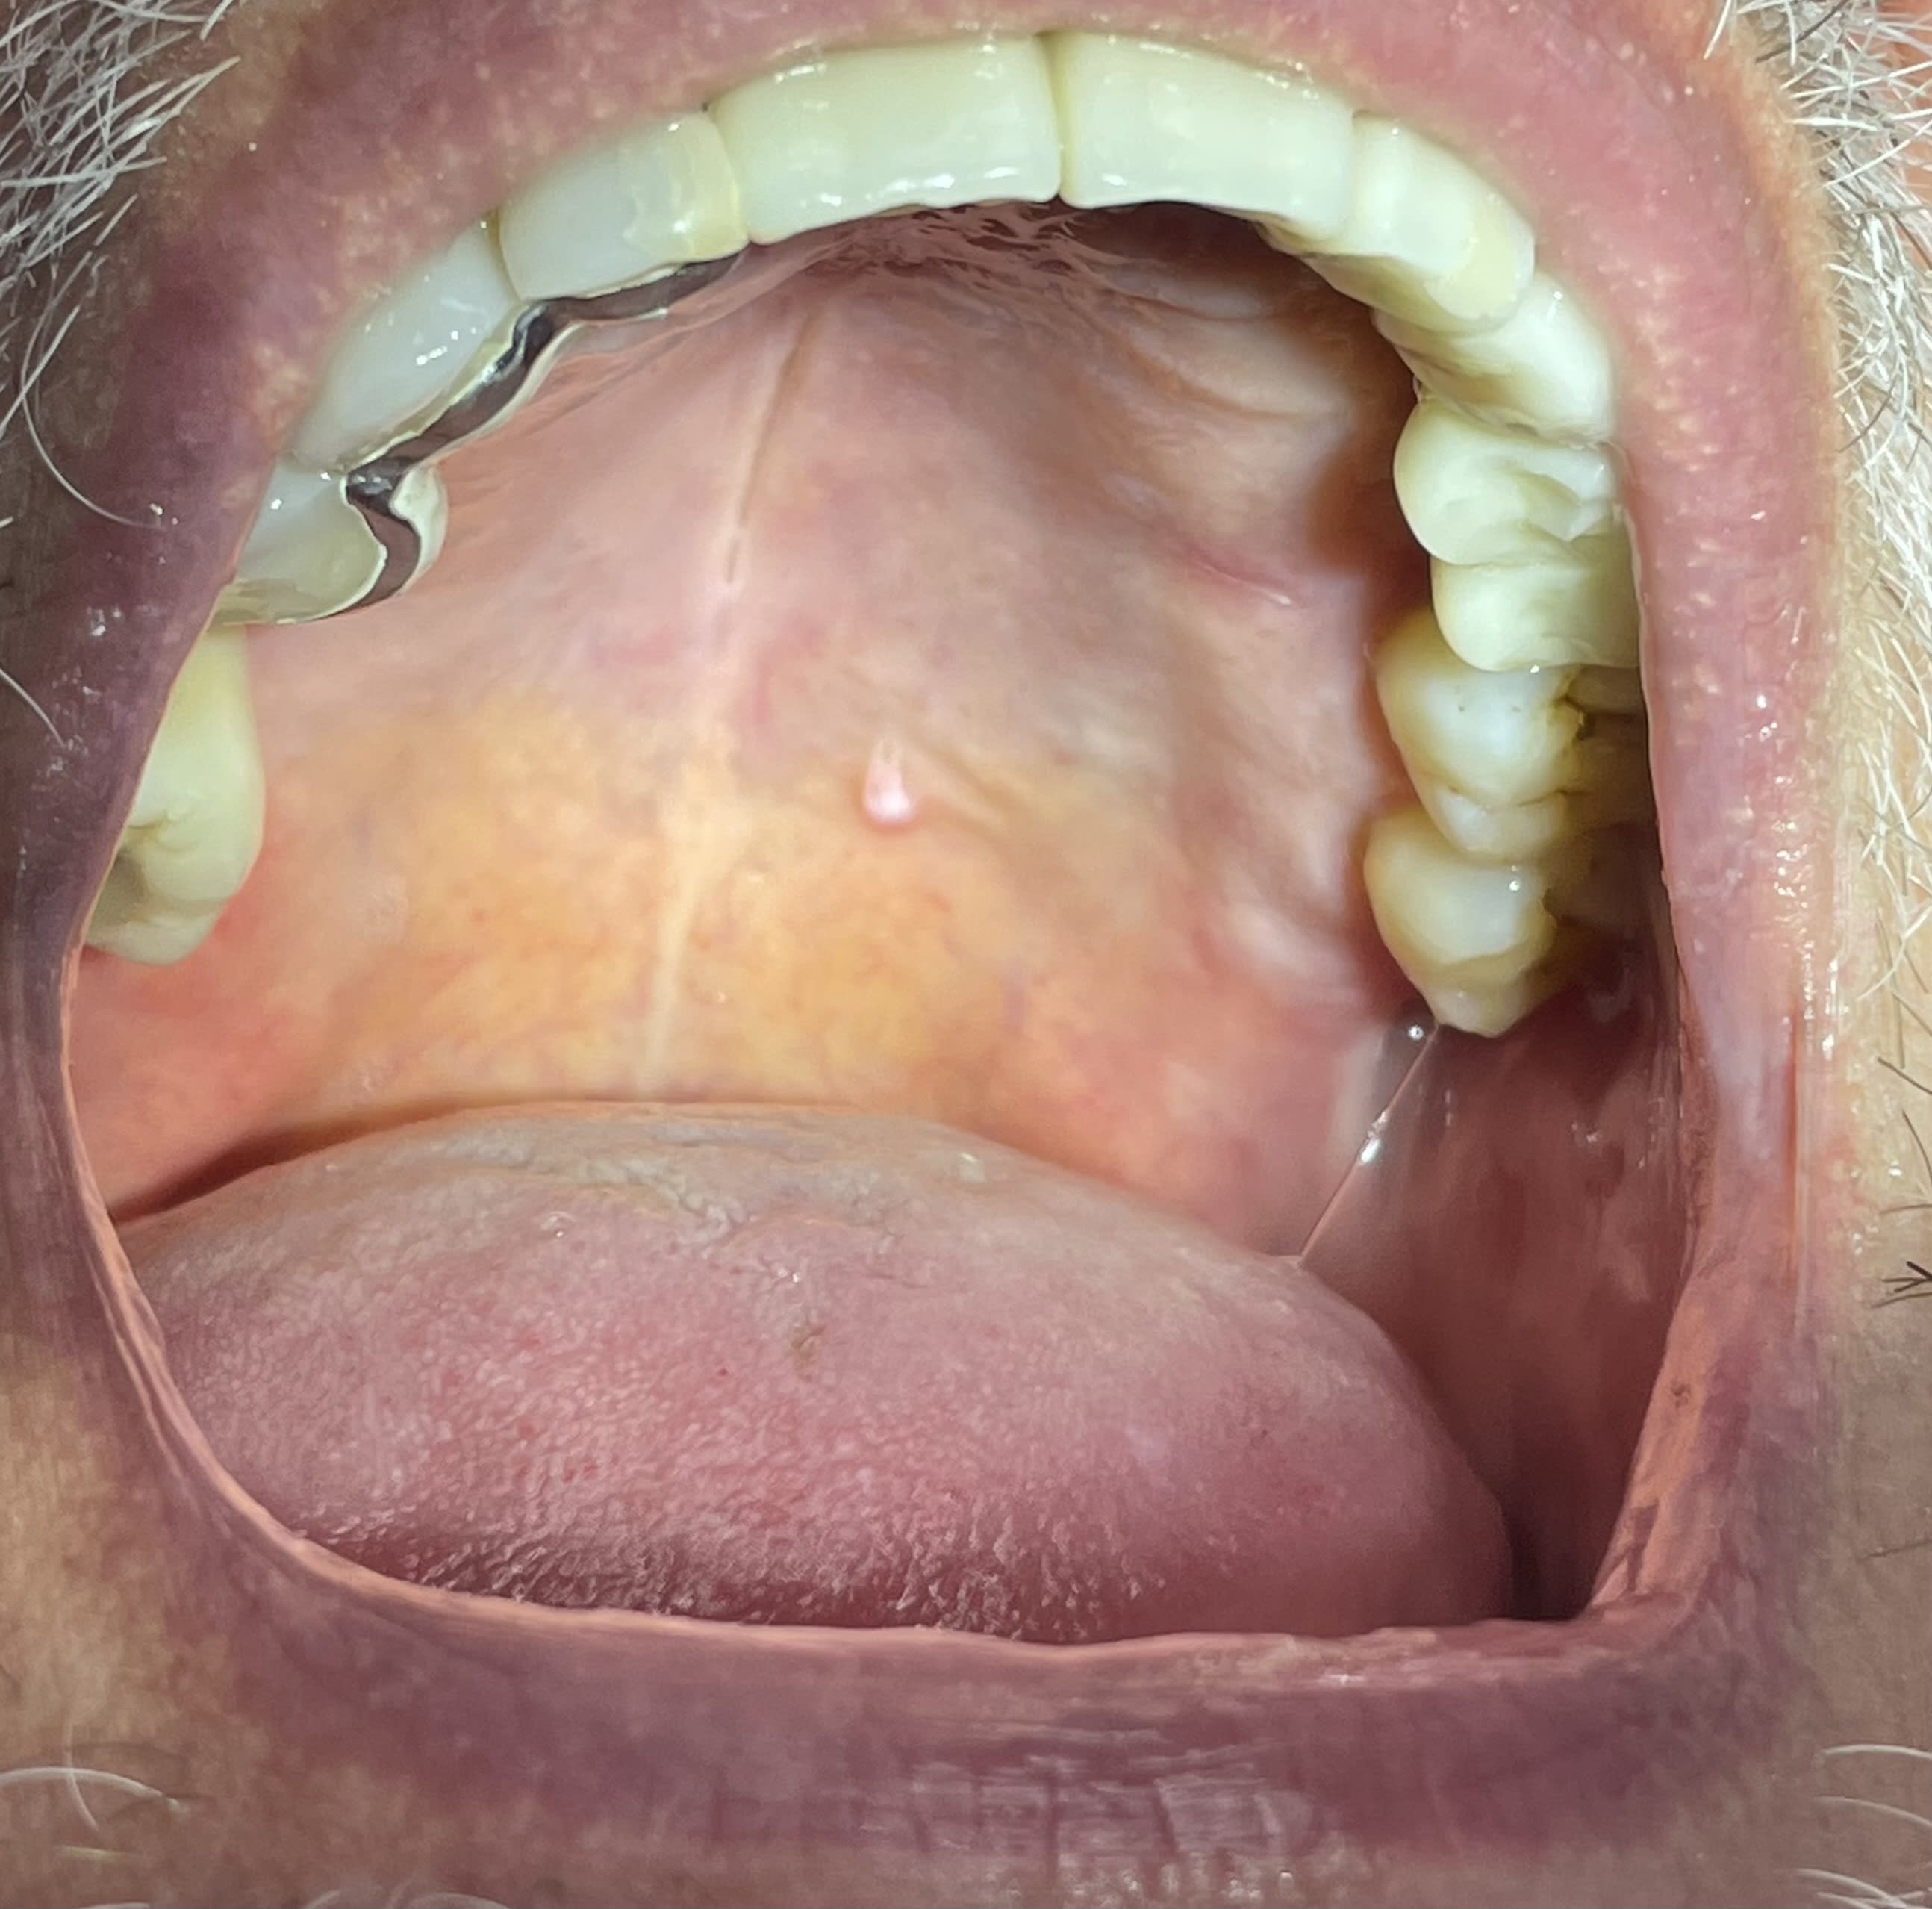

Que pensez vous de cette lésion au niveau du palais?

Totalement asymptomatique.

C'est un condylome/papillome lié très probablement à un HPV.

La plus part du temps c'est bénin, mais ca reste une lésion précancéreuse donc à surveiller.

Si ca prend une salle gueule, faire une exérèse et analyse en anapath.